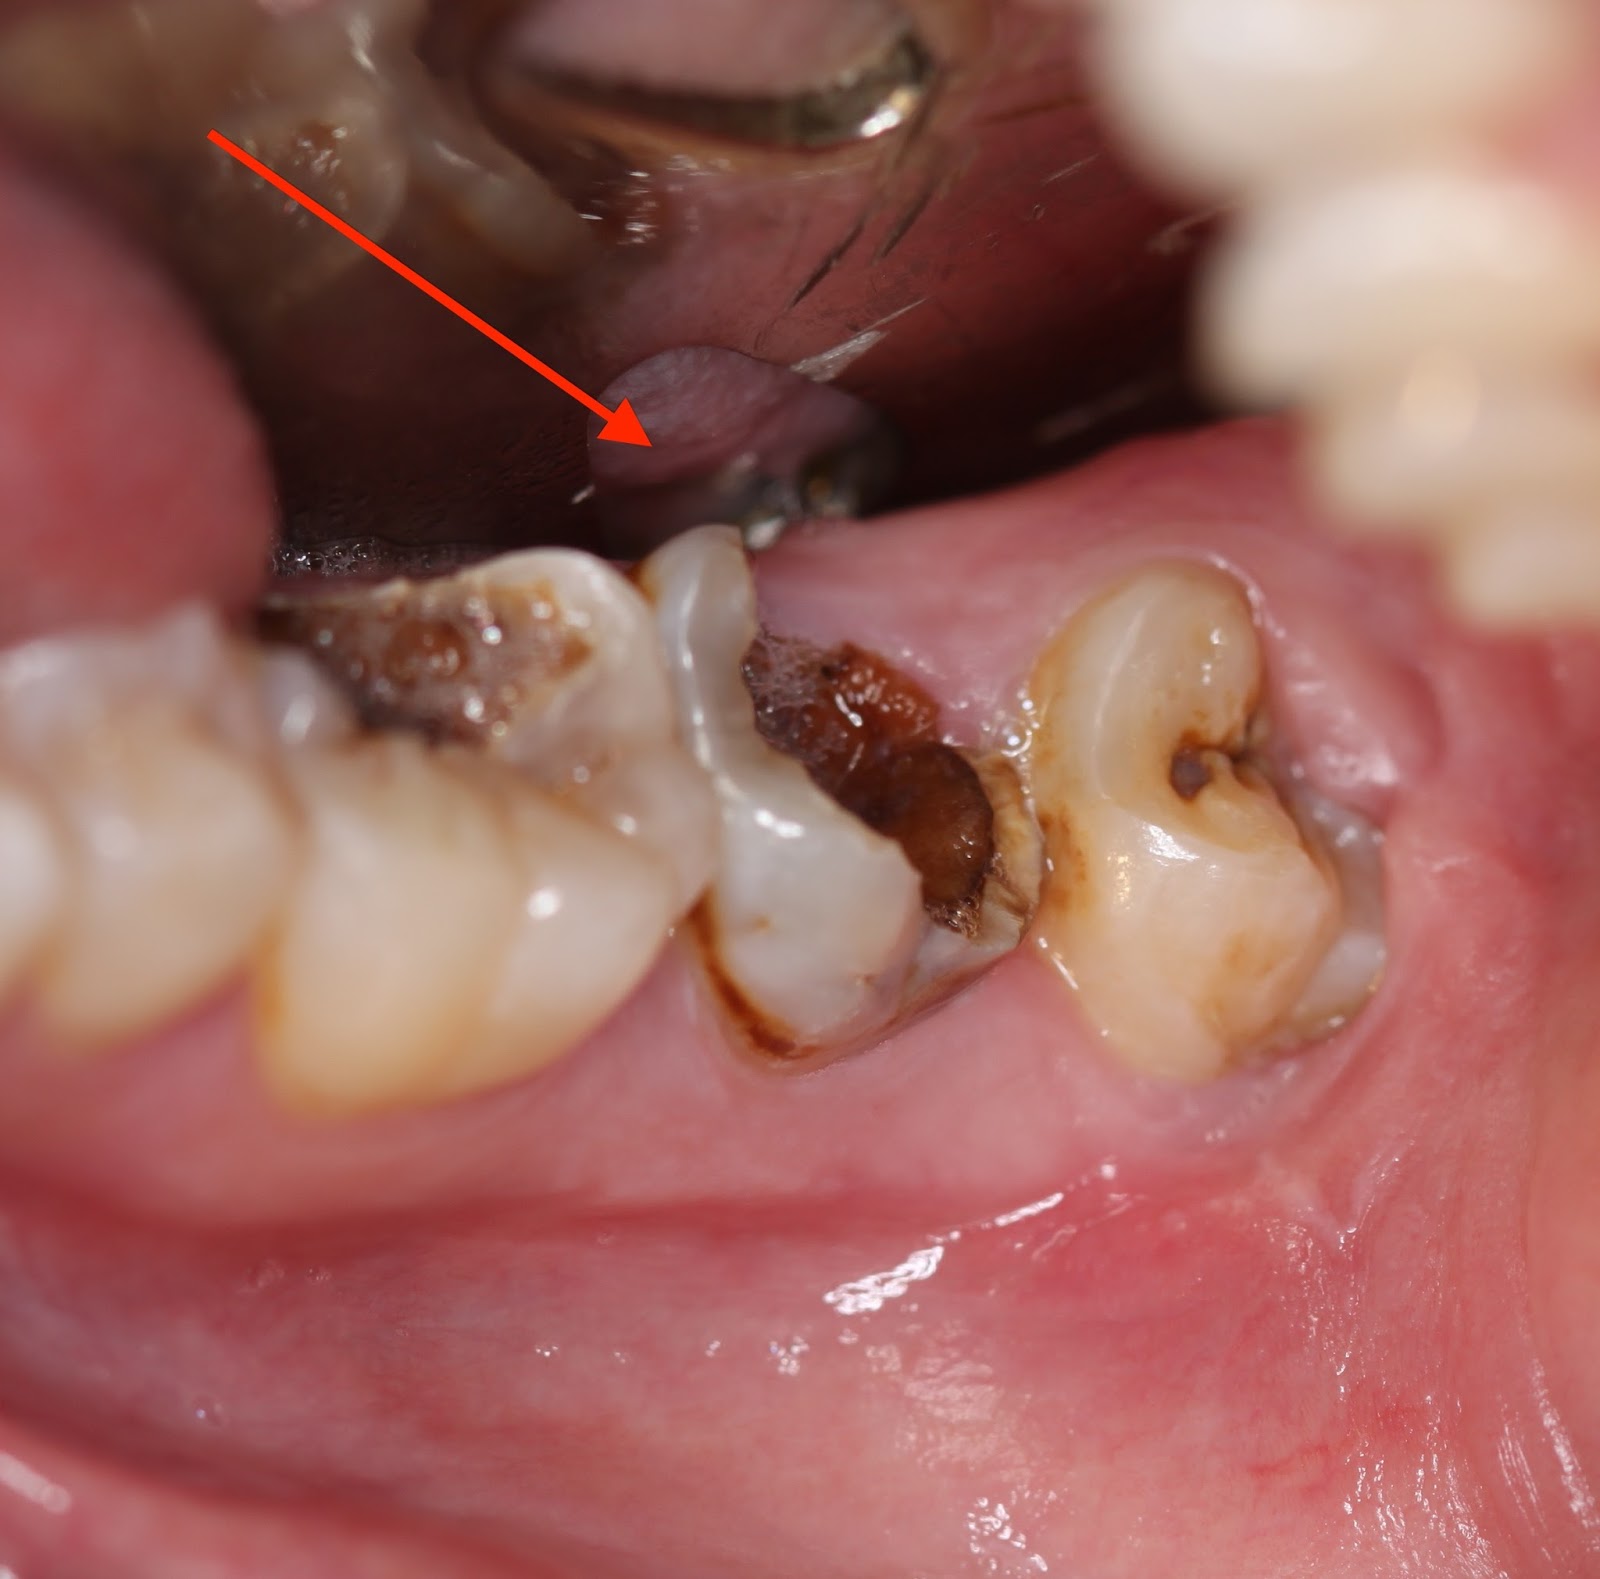

– Thứ nhất: Răng bị sâu nặng do vi khuẩn gây nên nhưng không được điều trị kịp thời. Vi khuẩn lan dần và xâm lấn đến buống tủy, dần dần dẫn đến tình trạng tủy bị viêm. Khi đó, điều trị lấy tủy sẽ là biện pháp duy nhất để loại bỏ các mô tủy bị hoại tử, giúp giữ được răng mà không cần nhổ bỏ, tránh viêm nhiễm xương ổ răng.

Răng sâu vào tủy có nên nhổ hay không sẽ dựa vào tình trạng cụ thể sau khi nha sỹ thăm khám. Bảo tồn chính là nguyên tắc đầu tiên trong điều trị nha khoa bởi răng sau khi nhổ cần phải trồng răng giả sớm để đảm bảo thẩm mỹ và ăn nhai, nhưng xét cho cùng thì răng giả không thể so sánh được với răng thật về cảm giác ăn nhai. Do đó, răng sâu dẫn đến viêm tủy chỉ nhổ bỏ khi không thể tiến hành bảo tồn bằng biện pháp điều trị nội nha được nữa.

Khi răng sâu tới tủy, vết sâu quá nặng, phần thân răng bị vỡ gần hết không thể hàn trám hay bọc sứ, tủy bị áp xe thì việc nhổ bỏ răng sâu là điều cần thiết. Một khi tủy gây áp xe xương ổ răng thì nguy cơ gây viêm nhiễm và ảnh hưởng đến các răng kế bên là không tránh khỏi. Bi dau rang sau phai lam sao?